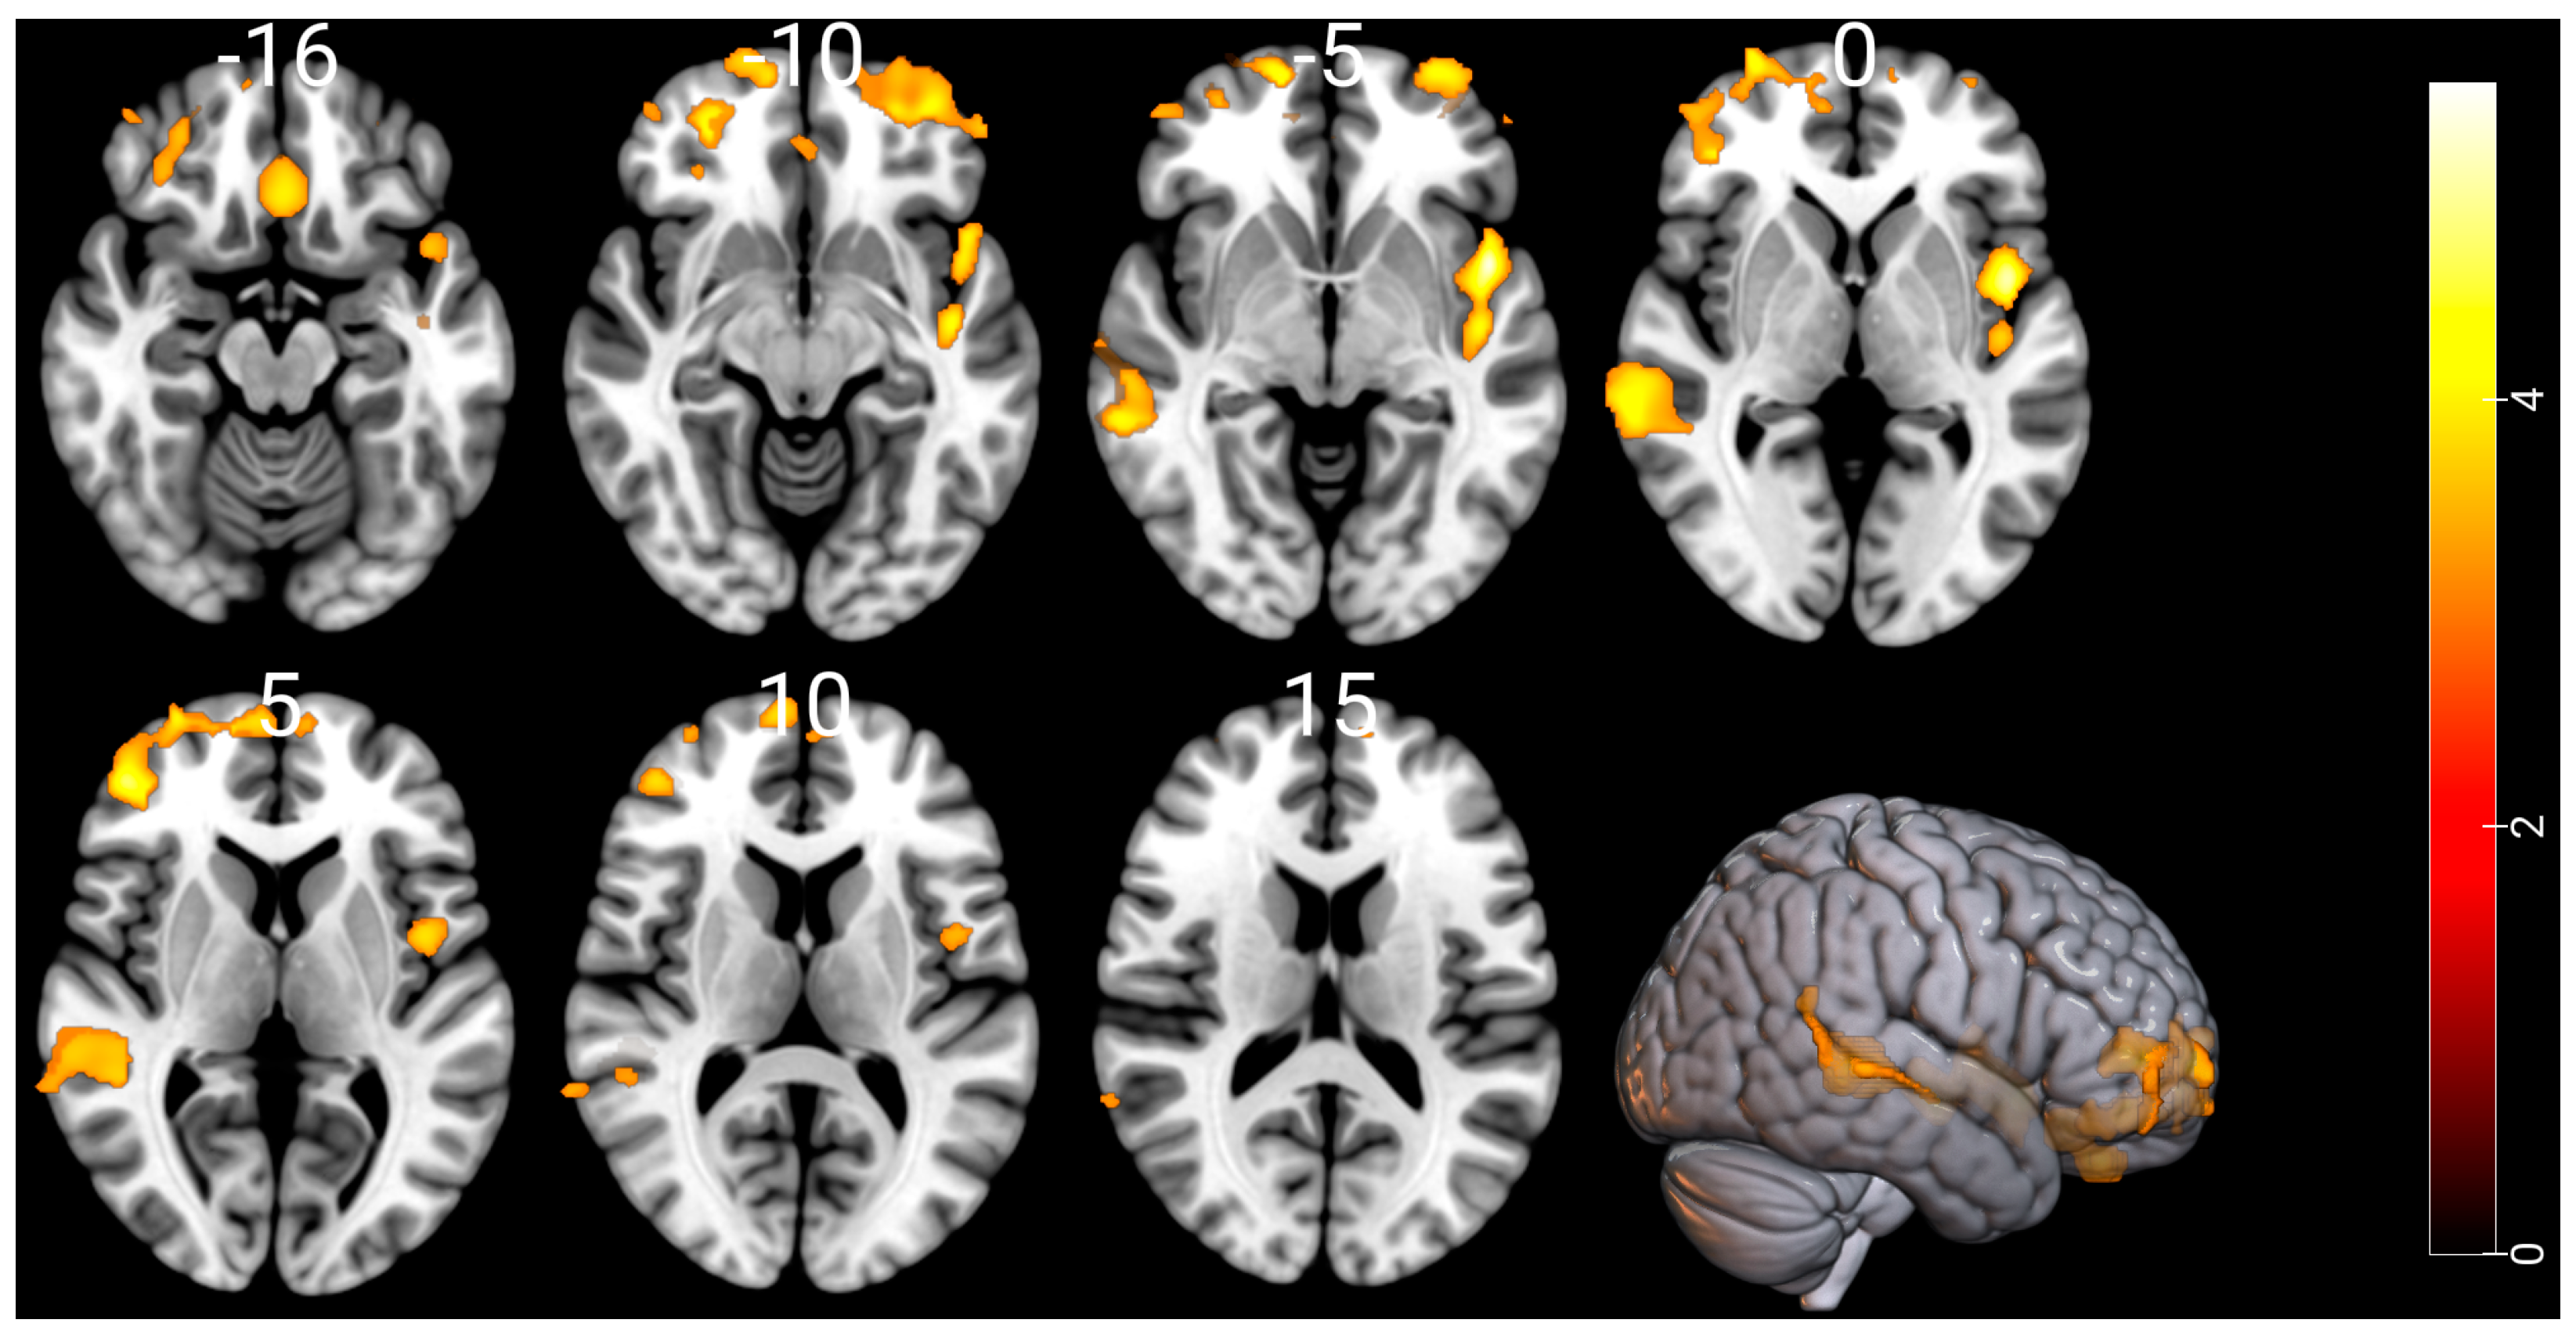

Compared with the HCs, the CUD patients showed a significant GM reduction in the temporal lobe, frontal lobe, insula, middle frontal gyrus, superior frontal gyrus, rectal gyrus and limbic lobe regions. Figure 1 and Table 2 show substantial GM atrophies detected by our whole-brain VBM analysis in the CUD patients versus HCs. The opposite contrast showed no significant GM swelling in the CUD patients when compared to the HCs. In the CUD group compared with the HCs or in the reverse contrast, the VBM and DBM analyses showed no significant alterations in WM and deep brain structures, respectively.

Figure 1.

Comparison of gray matter volume by VBM among 74 CUD patients and 62 HCs. Significant gray matter atrophy was observed in the temporal lobe, frontal lobe, insula, middle frontal gyrus, superior frontal gyrus, rectal gyrus, and limbic lobe regions in CUD patients compared to age- and sex-matched HCs. Substantial alterations are displayed as colored brain areas. The T-map was generated based on FDR-uncorrected at p < 0.001 with an extent threshold of k > 900. The color bar represents the t-test between the two groups. No gray matter swelling was detected in any region.